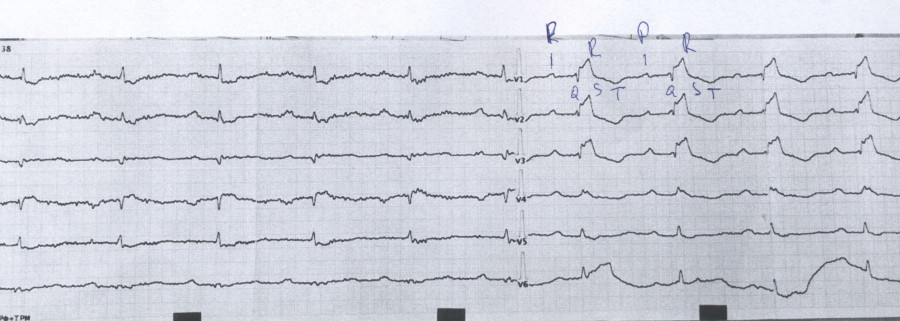

Это редкий врожденный порок сердца, при котором трехстворчатый клапан (раздел правое предсердие — правый желудочек) смещен вниз в полость правого желудочка. Это приводит к расширению правого предсердия, уменьшению полости правого желудочка и недостаточности клапана.